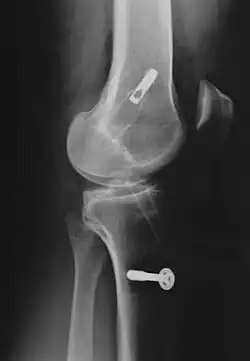

Röntgenaufnahmen leisten keinen unmittelbaren Beitrag zur Diagnosestellung einer Kreuzbandruptur. Beide Kreuzbänder sind – ob gerissen oder nicht – im Röntgenbild nicht sichtbar. Wird dennoch geröntgt, so kann dies der Diagnosestellung von möglichen knöchernen Begleitverletzungen dienen.

Bei der Rekonstruktion des Kreuzbandes mittels autologer Transplantation der Kniescheibensehne wird diese mit anhängenden Knochenteilen entnommen und durch verbreiterte Kanäle (8–10 mm Durchmesser) im Schienbein beziehungsweise Oberschenkelknochen gezogen. Die Länge des oberen und unteren Knochenblocks beträgt jeweils etwa 20 mm. Die stabilste Verankerung der Knochenenden des autologen Transplantats (englisch graft = Transplantate ohne Blutversorgung, weshalb sowohl hier als auch bei der im folgenden Abschnitt näher erläuterten Semitendinosustechnik von autograft gesprochen wird, mit altgriechisch αὐτός = selbst) wird durch die Fixation mit sogenannten Interferenzschrauben erreicht. Diese ist besonders wichtig im Hinblick auf eine frühe funktionelle Mobilisierung.

In den frühen 1990er Jahren wurden die Kniescheibensehnen-Transplantate mit sogenannten Titan-Interferenzschrauben als Fixation an beiden Enden des Transplantates, teilweise auch nur einseitig verschraubt und am Oberschenkelknochen mit einem sogenannten Endobutton, der durch das Transplantat „gefädelt“ wird, befestigt. Der Endobutton besteht aus einer Schlaufe aus einem nichtresorbierbaren Fadenmaterial mit einem Titan-Kipp-Knopf (Vierlochplatte), der nach der Durchführung durch den Knochenkanal verkippt wird.[178] Später wurden die Titanschrauben durch die heute verwendeten sogenannten Bio-Screws („Bio-Schrauben“, das sind autobioresorbierbare Interferenzschrauben) ersetzt,[179] die einen erneuten Eingriff zur Materialentfernung unnötig machen. Diese Schrauben bestehen aus abbaubaren Polymeren, wie beispielsweise Poly-L-Lactid (PLLA) oder Poly-(L-co-D/L-Lactid) (PLDLLA). Ebenso kann eine Hybridtechnik aus Bio-Schraube (als intraartikuläre Fixation) und femorale/tibialen Endobuttons (als extraartikuläre Fixation) durchgeführt werden. Bei der sogenannten „Press-Fit-Technik-Fixation“, die um das Jahr 1995 aufkam, kann auf die Schraubenfixation bei der BTB-Technik (Knochen-Sehne-Knochen-Technik) völlig verzichtet werden. Hierbei werden die Knochenenden konisch zugerichtet, sodass ein festes Verkanten in den Bohrkanälen gewährleistet ist. Ab 1996 kamen Operationsroboter auf, die den Bohrkanal automatisch mit einem Diamantfräskopf erzeugten. Sie konnten sich nicht durchsetzen, weil sie keine eindeutig besseren operativen Ergebnisse hervorbrachten und hohe Kosten (personal- und apparateintensiv) verursachten.

Sonderfall knöcherner Ausriss

Der knöcherne Ab- oder Ausriss des vorderen Kreuzbands vom Knochen (Schienbein oder Femur) ist wesentlich seltener als seine intraligamentäre Ruptur[255] und ist definitionsgemäß kein Kreuzbandriss. Dieser Sonderfall tritt häufiger bei Kindern, vor allem im Bereich des Kreuzbandansatzes am Schienbein Eminentia intercondylica auf und hat durch Refixierung des Ausrisses – beispielsweise mit Schrauben oder Drahtnaht – allgemein gute Chancen, wieder vollständig knöchern einzuheilen. Bei der arthroskopischen Refixation der das Kreuzband tragenden Knorpel-Knochen-Schuppe ist eine gute Übersicht von entscheidender Bedeutung, um die Einklemmung des Ligamentum transversum genus (zwischen den Menisken) unter dem Fragment zu vermeiden. Ansonsten ist die Mini-open-Technik vorzuziehen. Generell ist darauf zu achten, mit den Implantaten (Schrauben oder Drahtnähten) die Wachstumsfuge nicht zu blockieren.